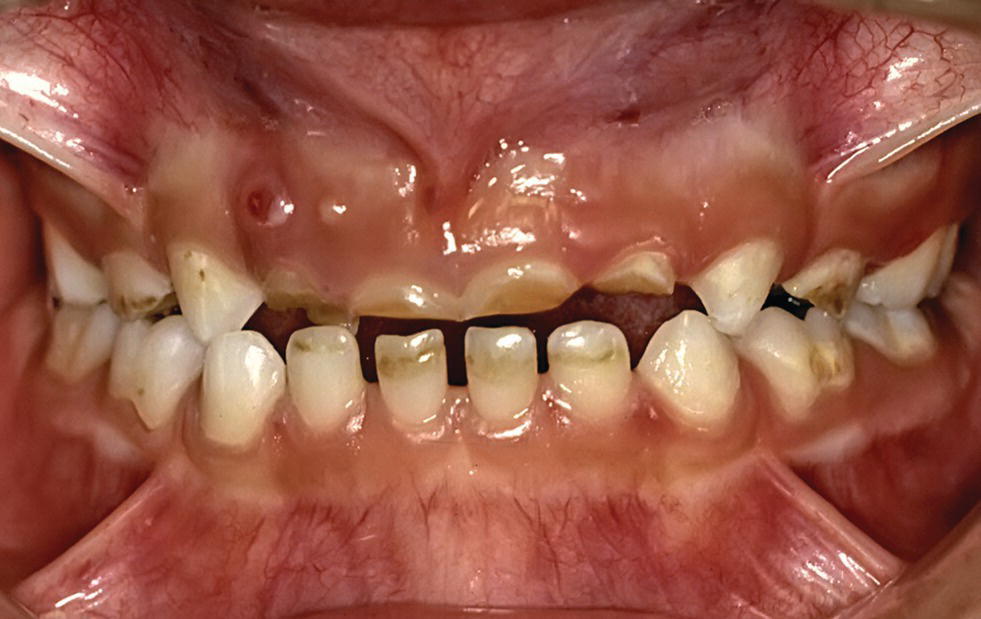

When The Enamel Is Worn Away, The Dentine Underneath Is Exposed, Which May Lead To Pain And Sensitivity.

Web tooth erosion happens when acids wear away the enamel on teeth. Web what is tooth erosion? Web tooth erosion occurs when excess acid wears away the tooth enamel, which is the hard, outer layer that gives teeth their structure.

Enamel Erosion Can Be Caused By The Following:

Drink fluoridated tap water rather than soft drink or juice. Teeth grinding chronic acid reflux, also known as gastroesophageal reflux disease (gerd) low salivary flow, also known as xerostomia, which is a symptom of conditions like diabetes regular use of certain medications, such as antihistamines and aspirin eating. In general, the calcium that occurs naturally in saliva will help neutralize the acid in the foods you.

Web Tooth Erosion May Occur As A Result Of:

Web erosion is the loss of tooth enamel caused by acid attack. Web to reduce your risk of tooth erosion: When the enamel is worn away, the dentine underneath is exposed, which may lead to pain and sensitivity.